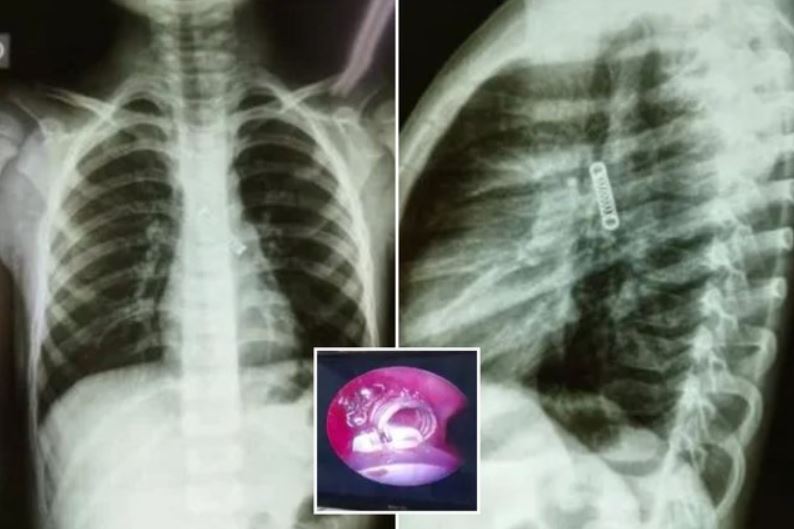

Prej tre muajsh kishte gëlltitur një sustë metalike e cila i kishte përfunduar më pas në mushkëri! Dhe fëmija ishte vetëm 5 vjeç. Një fëmije…